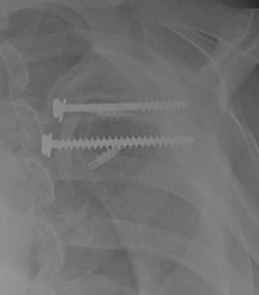

Medial row anchors and lateral screws for missed lesser tuberosity avulsion in adolescent

Screw + soft tissue washer

LTLTlt